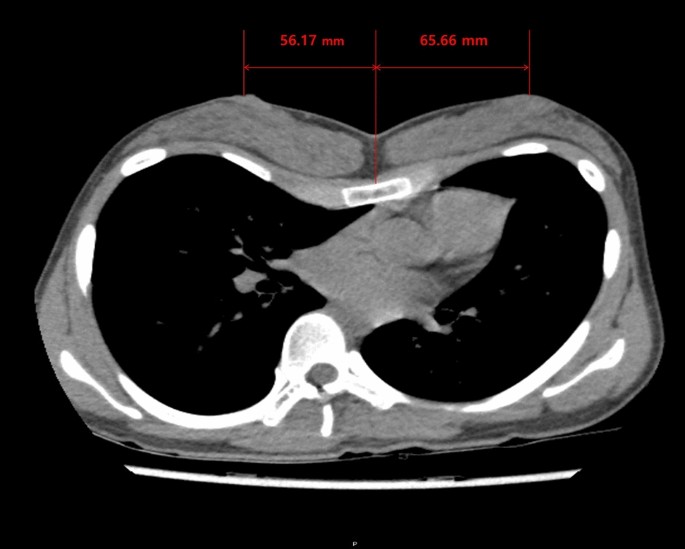

Because the breast strabismus causes a diminished intermammary distance with strabismus of the nipple-areola complexes, reposition of the breasts to an aesthetically acceptable position in women pectus excavatum patients following Nuss procedure is seemed to show increasing the intermammary distance. However, there have been no studies of properly quantified intermammary distance changes before and after pectus excavatum repair in women pectus excavatum patients. Because the breast is a three-dimensional structure, that shape can be expressed with a variety of indicators. Although simple numerical values are insufficient as a means of the breast shape expression, the authors quantified the pre- and postoperative changes in the distance between nipples by measuring the distance between them on the chest CT sections (Fig. 2).

Based on chest CT, we used the Picture Archiving Communication System (PetaVision, Seoul, Korea) to measure the distance between the sternal midline and the patients’ nipples on the left and right sides. We calculated the distance between the nipples by adding the right and left distances together (Fig. 3).